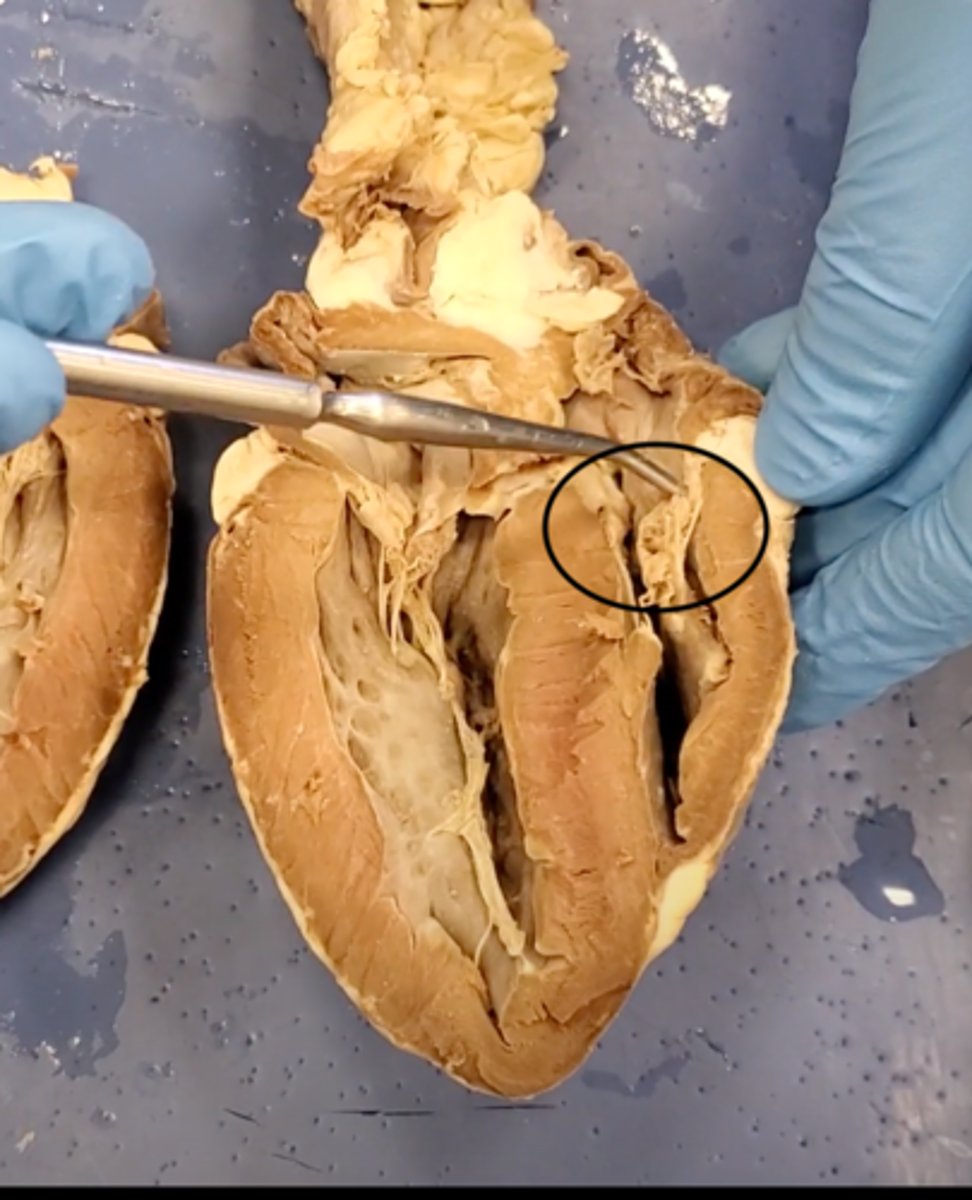

Tricuspid Valve (Right Atrioventricular Valve)

1-valve

Bicuspid valve (Left Atrioventricular Valve)

2-valve

Pulmonary Semilunar Valve

3-valve

Aortic Semilunar Valve

4-valve

Right Atrium

1-chamber

Left Atrium

2-chamber

Right Ventricle

3-chamber

Left Ventricle

4-chamber

Inferior Vena Cava

5-A vein that is the largest vein in the human body and returns blood to the right atrium of the heart from bodily parts below the diaphragm.

Superior Vena Cava

6-A vein that is the second largest vein in the human body and returns blood to the right atrium of the heart from the upper half of the body.

Aorta

7-The large arterial trunk that carries blood from the heart to be distributed by branch arteries through the body.

Pulmonary Trunk

8-carries blood from right ventricle to pulmonary arteries

Pulmonary veins

9-a vein carrying oxygenated blood from the lungs to the left atrium of the heart.

yellow sash of fat that tells you this if the front side of the heart (dissection)

pulmonary trunk (dissection)

t-shaped ribbon of fat on back side of heart (dissection)

left auricle (dissection)

right auricle (dissection)

left ventricle (dissection)

right ventricle (dissection)

right atrium (dissection)

left atrium (dissection)

bicuspid valve (dissection)

tricuspid valve (dissection)

aortic semilunar valve (dissection)

located between the left ventricle and the aorta

chordae tendineae (dissection)

thin bands of fibrous tissue that attach to the valves in the heart and prevent them from inverting